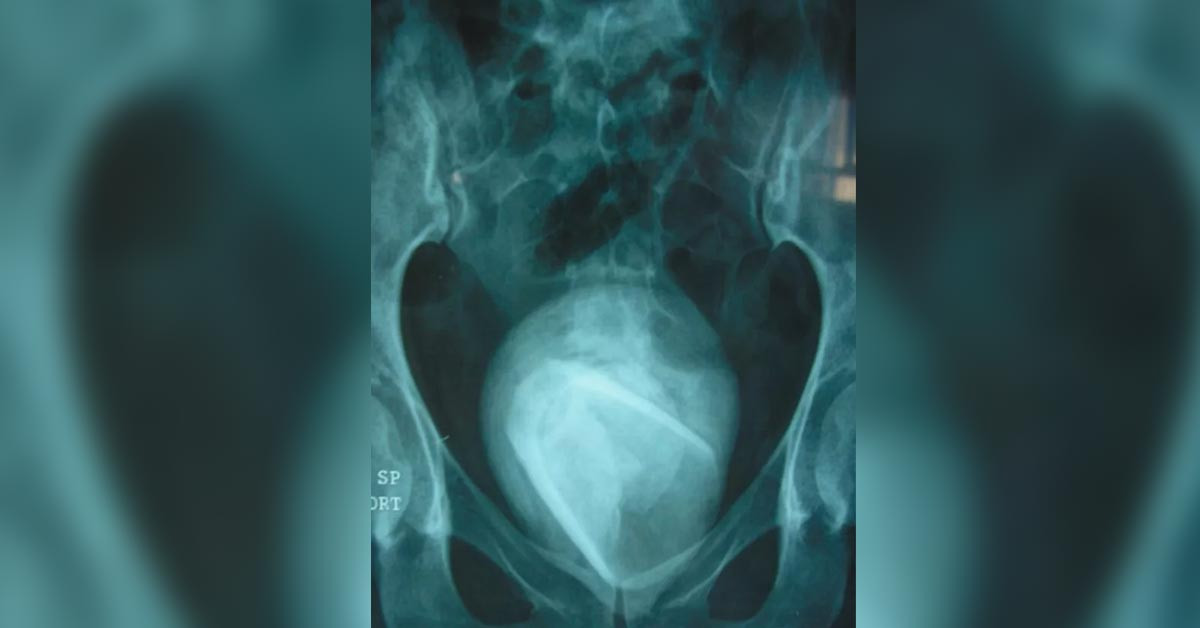

Detaylı bir taramanın ve röntgenin ardından 45 yaşındaki kadının mesanesinde cam bardak çıktı! Cam bardağın 4 yıldır kadının içinde olduğu öğrenildi.

Durumu öğrenen kadın şok olmuştu. Yıllardır duran cam bardağın dışı zamanla mesane taşıyla çevrilmiş. Bu yüzden kimse fark edememiş.

Kadının mesanesindeki cam bardak idrar yollarını tıkadığı için yıllar içinde bardağın etrafı sert mineral kütleler tarafından sarılmış.

Resim gördüğünüz şey kadının içinden çıkan cam bardak ve tabaka.